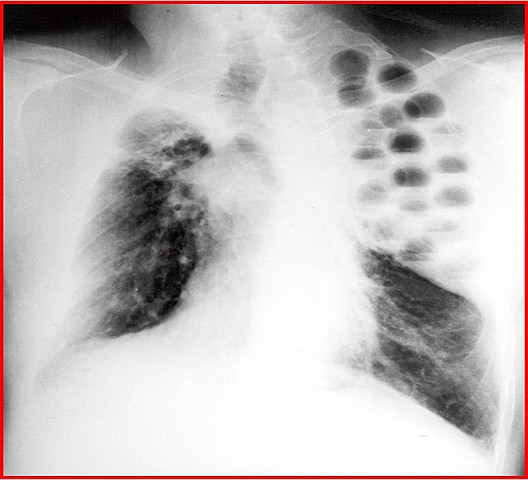

Tuberculosis

Enfermedad infecciosa y transmisible, aislamiento de la bacteria.